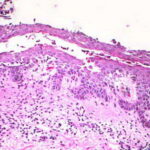

Histopathology. The earliest change consists of acantholysis in the upper epidermis, within or adjacent to the granular layer, leading to a subcorneal bulla in some instances . More commonly, enlargement of the cleft leads to detachment |

of the stratum corneum without bulla being seen. The number of acantholytic keratinocytes is usually small, often requiring a careful search to identify them. Secondary clefts may develop, leading to detachment of the epidermis in its mid level. These clefts may extend to above the basal layer, rarely giving rise to limited areas of suprabasal separation. In the setting of a subcomeal blister, dyskeratotic granular keratinocytes are diagnostic for this disorder. Eosinophilic spongiosis may be prominent with intraepidermal eosinophilic pustules. Thus, the histologic features of pemphigus foliaceus may have three pattems: {a} eosinophilic spongiosis; {b} a subcorneal blister, often with few acantholytic keratinocytes; and {c} a subcorneal blister with dyskeratotic granular keratinocytes , diagnostic of this disorder. The character of the inflammatory infiltrate is variable and depends on the age of the lesion, whether a blister is present, whether the superficial portion of the epidermis has been detached, and whether there is impetiginization or necrosis of the blister roof. |